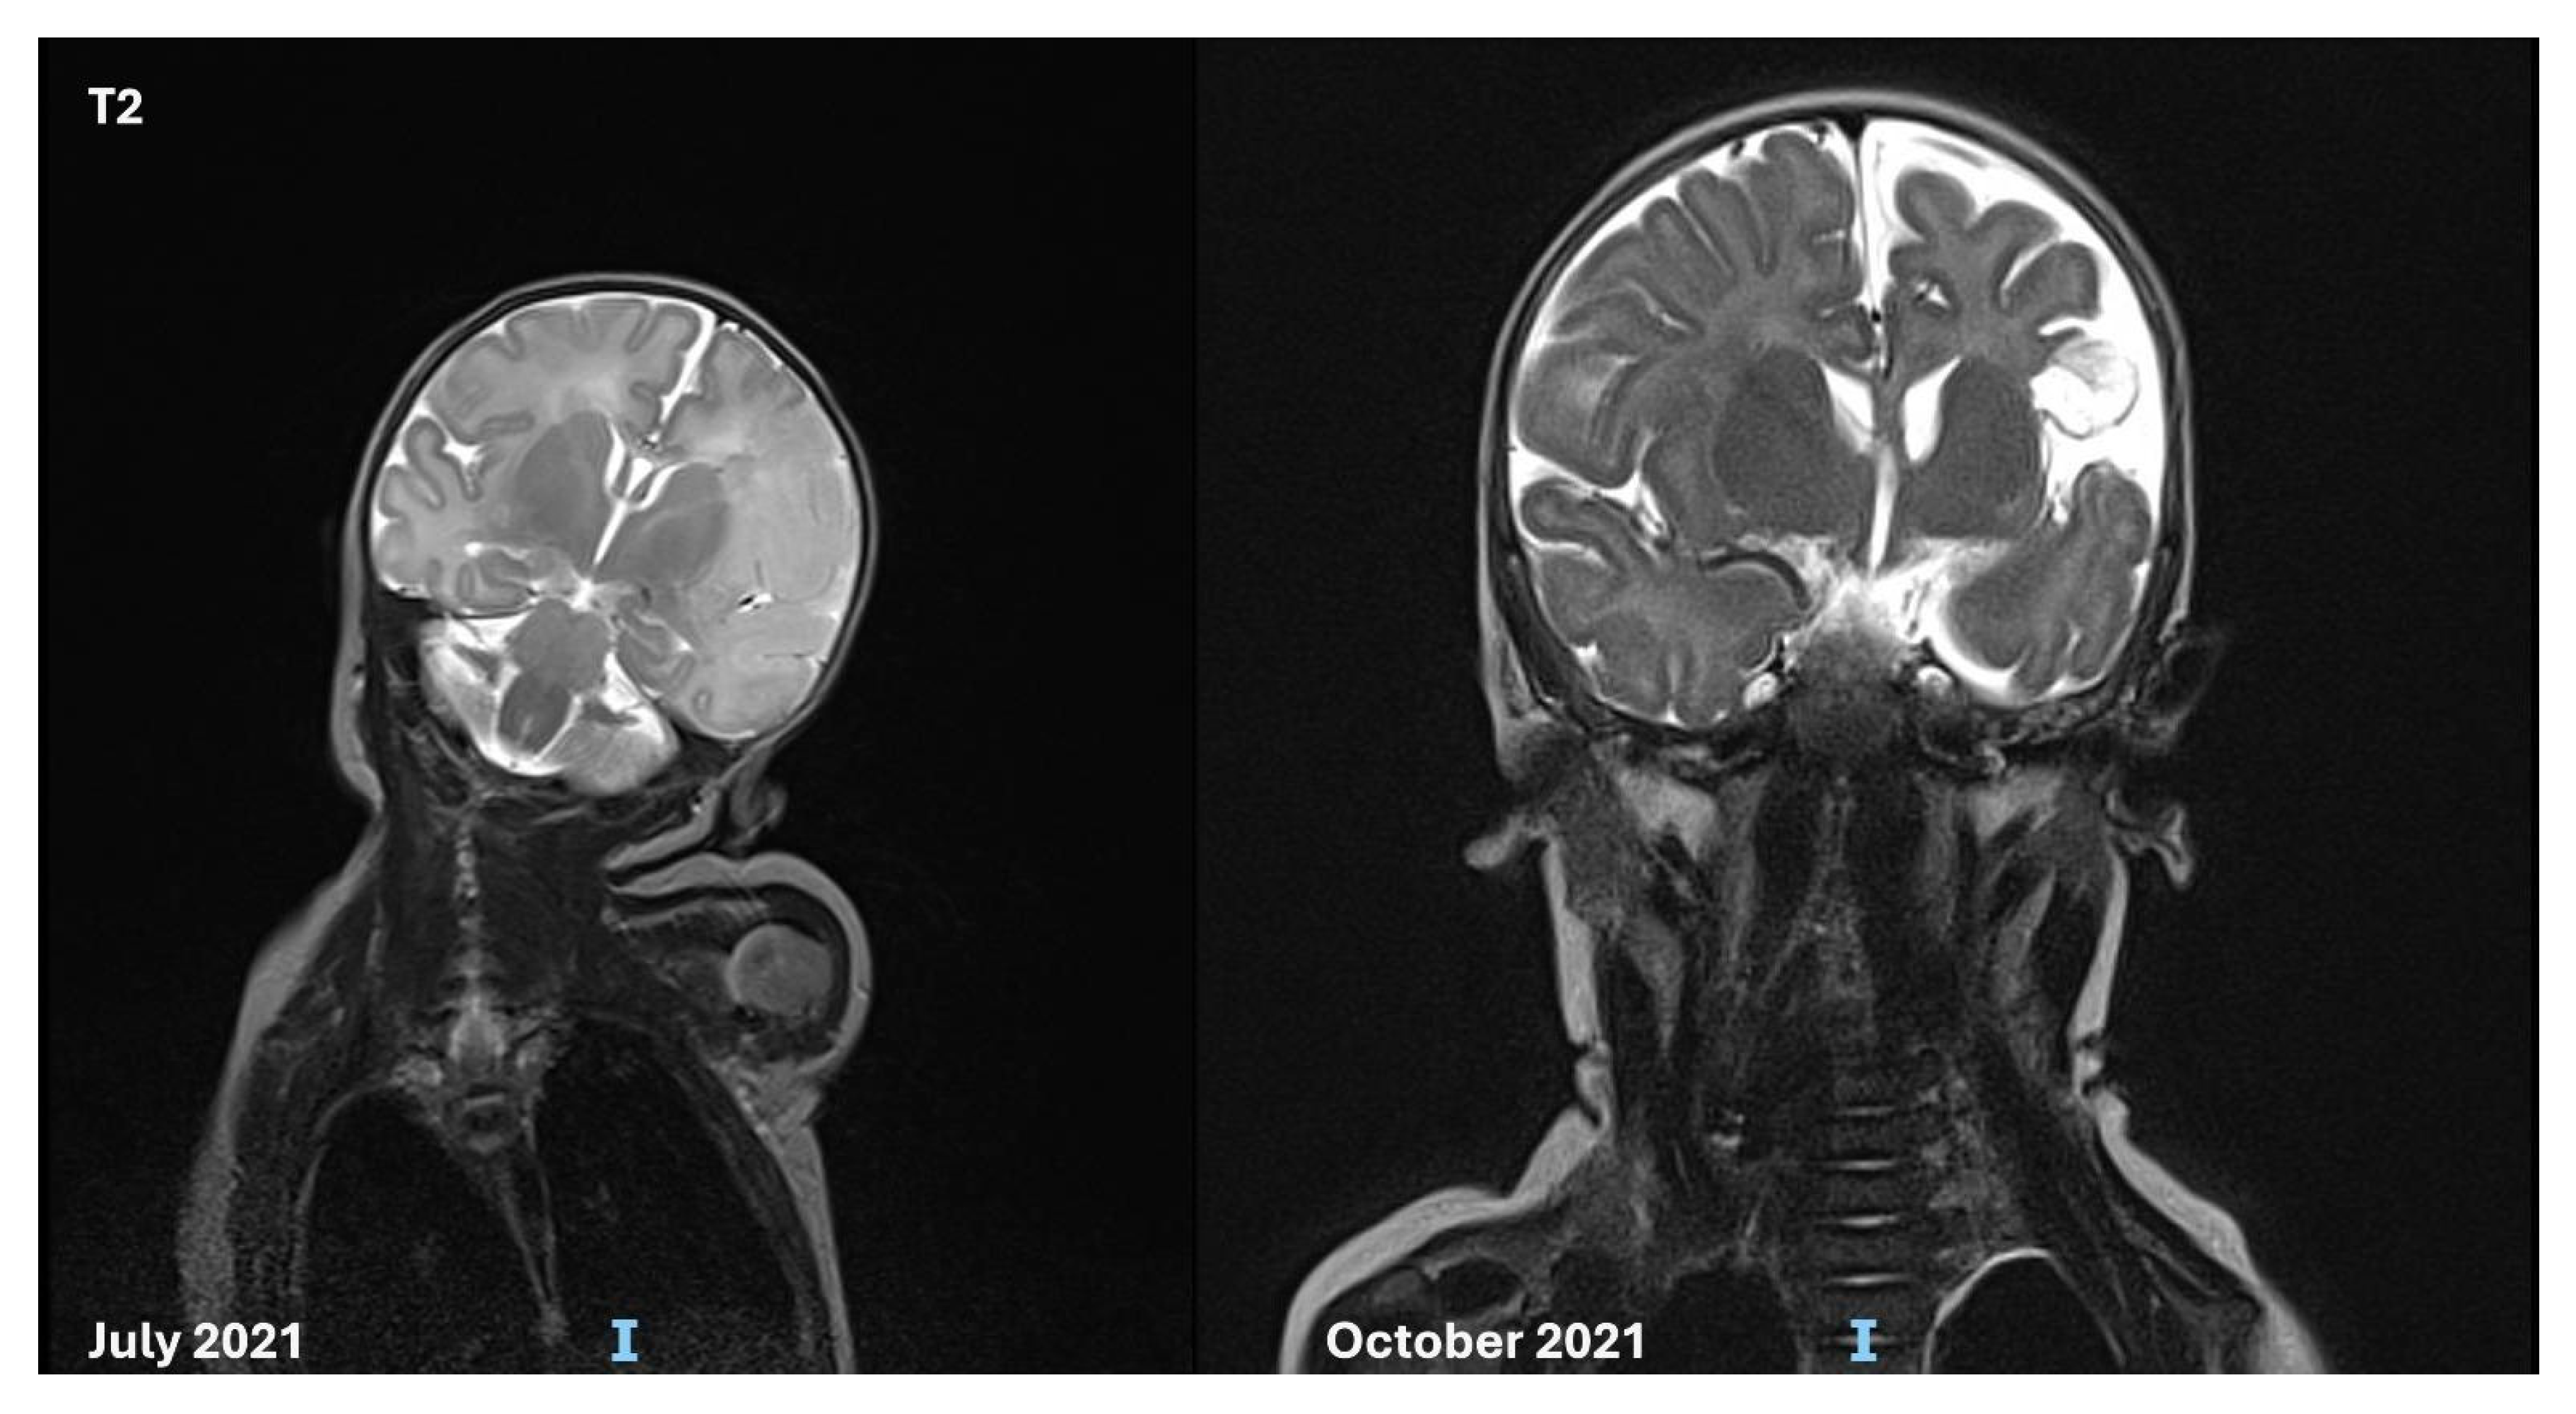

3.3. Follow-up and Neurodevelopmental Outcomes